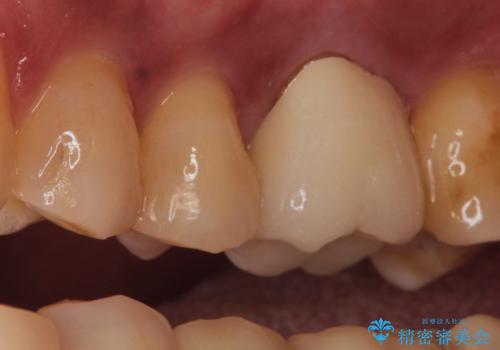

根管治療を行ったのち、症状改善を認めオールセラミッククラウンにて修復治療を行いました。

根管治療を行った歯は、再発防止や残された歯質を守るため、クラウンによる補綴治療が必要となります。